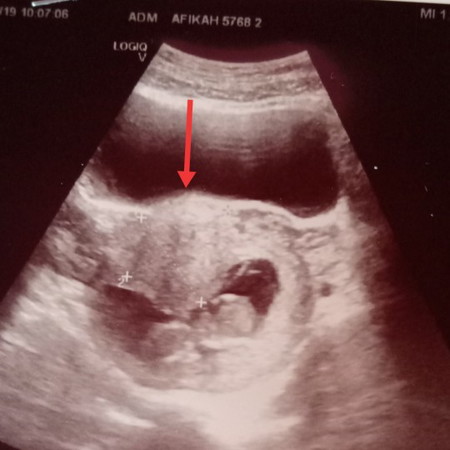

fibroid

Ada x momies2 yg ada mcm sy, ade fibroid?? sy bru 12week++ hri ni scan doc ckp ada fibroid 4cm.. Risau n takut plk?

Ada fibroid yg terjadi disebab kan hormon mengandung tggi.. Tu yg buat dia aktif.. Pernah tnya doc dlu, mknn apa yg xboleh makan.. Dia kata, mknn bukan effect besar sgt buat fibroid tu besar.. Kdg kala hormon kita.. Tgk jugak kedudukan fibroid tu kt mana.. Bahaya kalau dia halang laluan rahim sbb ttup laluan nak branak.. Kalau de fibroid mesti akan follow up dgn pakar.apa2 rujuk doc sebab kita pregnant.. So kena selalu follow up dgn doc.